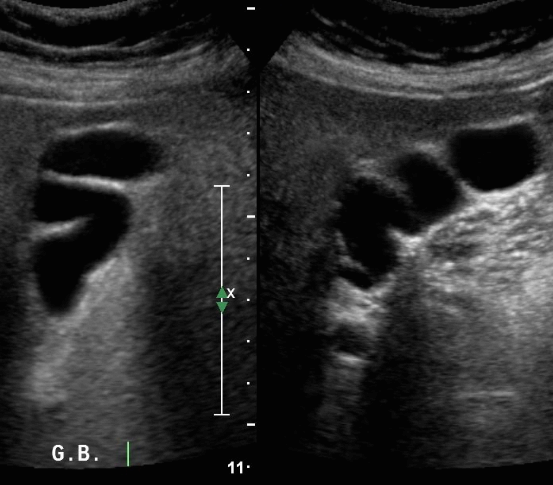

담낭의 정상변이 (normla variation)

1) Folder GB

해부학적 정상변이로 담낭이 굴곡된 상태이고 환자의 15% 에서 관찰된다. 담석이 자주 보이므로 환자 체위를 변화시켜 검사해야 한다.

2) Phrygian cap

해부학적 정상변이로 담낭 저부에 격막에 의한 주름이 형성된 상태이고 환자의 6%에서 관찰된다. 게실형태로 담낭 내강을 충분히 검사하기 어려우며 캡에 결석이 존재할 가능성이 있으므로 환자의 체위를 변화시켜 검사해야 한다.